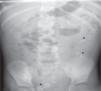

Se realizan una radiografía simple de abdomen y una ecografía abdominal, donde se aprecian litiasis renovesicales, nefromegalia izquierda e imágenes sugestivas de pionefrosis (figs. 1 y 2).

A) Focos cálcicos con sombra acústica posterior indicativos de litiasis vesicales. B) Nefromegalia izquierda y dilatación pielocalicial con contenido espeso ecogénico indicativo de pionefrosis. Pobre diferenciación corticomedular y focos cálcicos con sombra posterior en pelvis renal izquierda.